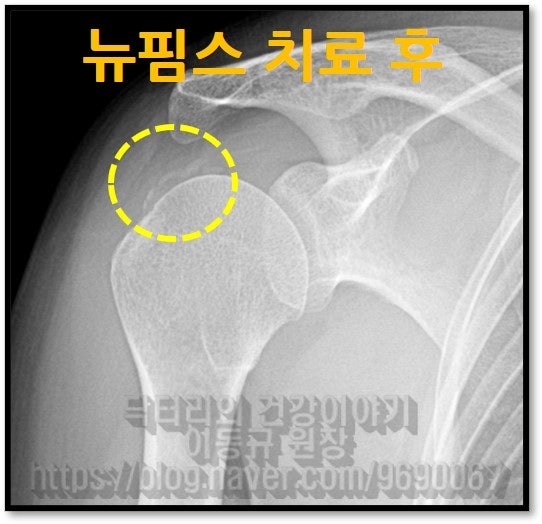

이렇게 석회를 분쇄해서 흡입을 하게 되고 뉴핌스치료(석회분쇄흡입술) 후 찍은 X-ray를 보면

시술 후 통증이 확연하게 감소 되었고 환자는 아주 만족해 하셨습니다. 아직 남아있는 석회에 대해서는 추가적인 충격파 치료를 통해 치료를 하면 됩니다. 어깨 석회성 건염은 수술 없이 나을 수 있는 질환입니다. 물론 회전근개 파열이 동반되어 있다면 파열의 양상에 따라서는 다르겠지만 수술이 필요할 수도 있습니다. 하지만 석회성 건염만 있다면 수술을 필요치 않다고 생각합니다.